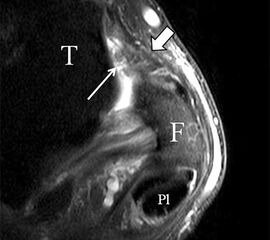

Das Ligamentum fibulotalare anterius entspricht einer bifaszikulären Struktur (Abb. 2 a) mit interponierendem fibrovaskulärem Gewebe (S. K. Sarrafian (ed). 2003). Es gibt jedoch Variationen der Ligamentanatomie. In 55% liegt das LFTA als bifaszikuläres Band (Abb. 2 a), in 9% als monofaszikuläre Bandstruktur (Abb. 2 b) und in 36% als multifaszikuläre, striäre Variante (Abb. 2 c) vor 3.

PD fs HR axial. Klare Darstellung eines filigranen, knapp über 1 mm breiten LFTA (Pfeil). Fibula (F).

Abbildung 3

Das LFTA verbindet die antero-inferiore Fibulaspitze mit dem Processus lateralis tali und inseriert hier an einem oder zwei kleinen Tuberkeln 3. Der in Neutralposition horizontale Verlauf erleichtert die kernspintomographische Darstellung in dieser Standardebene. Das LFTA weist durchschnittlich eine Breite von knapp über 2 mm auf 4. Somit sind bei einer Routinedarstellung in 3 mm Schichtdicke Anschnittsphänomene, die die Diagnostik erschweren, regelmäßig anzutreffen. Dementsprechend sind auch die ligamentären Subfaszikel nicht zu differenzieren. In koronarer Darstellung ist dies aufgrund der hohen Auflösung in der Schichtebene jedoch möglich (Abb. 2 a-c), wobei hier wiederum eine Integritätsbeurteilung des Bandes erschwert ist. Unter Verwendung hochauflösender Techniken im Millimeterbereich (Schichtdicke) sind hingegen auch in der axialen Ebene die subfaszikulären Strukturen zu beurteilen (Abb. 3).